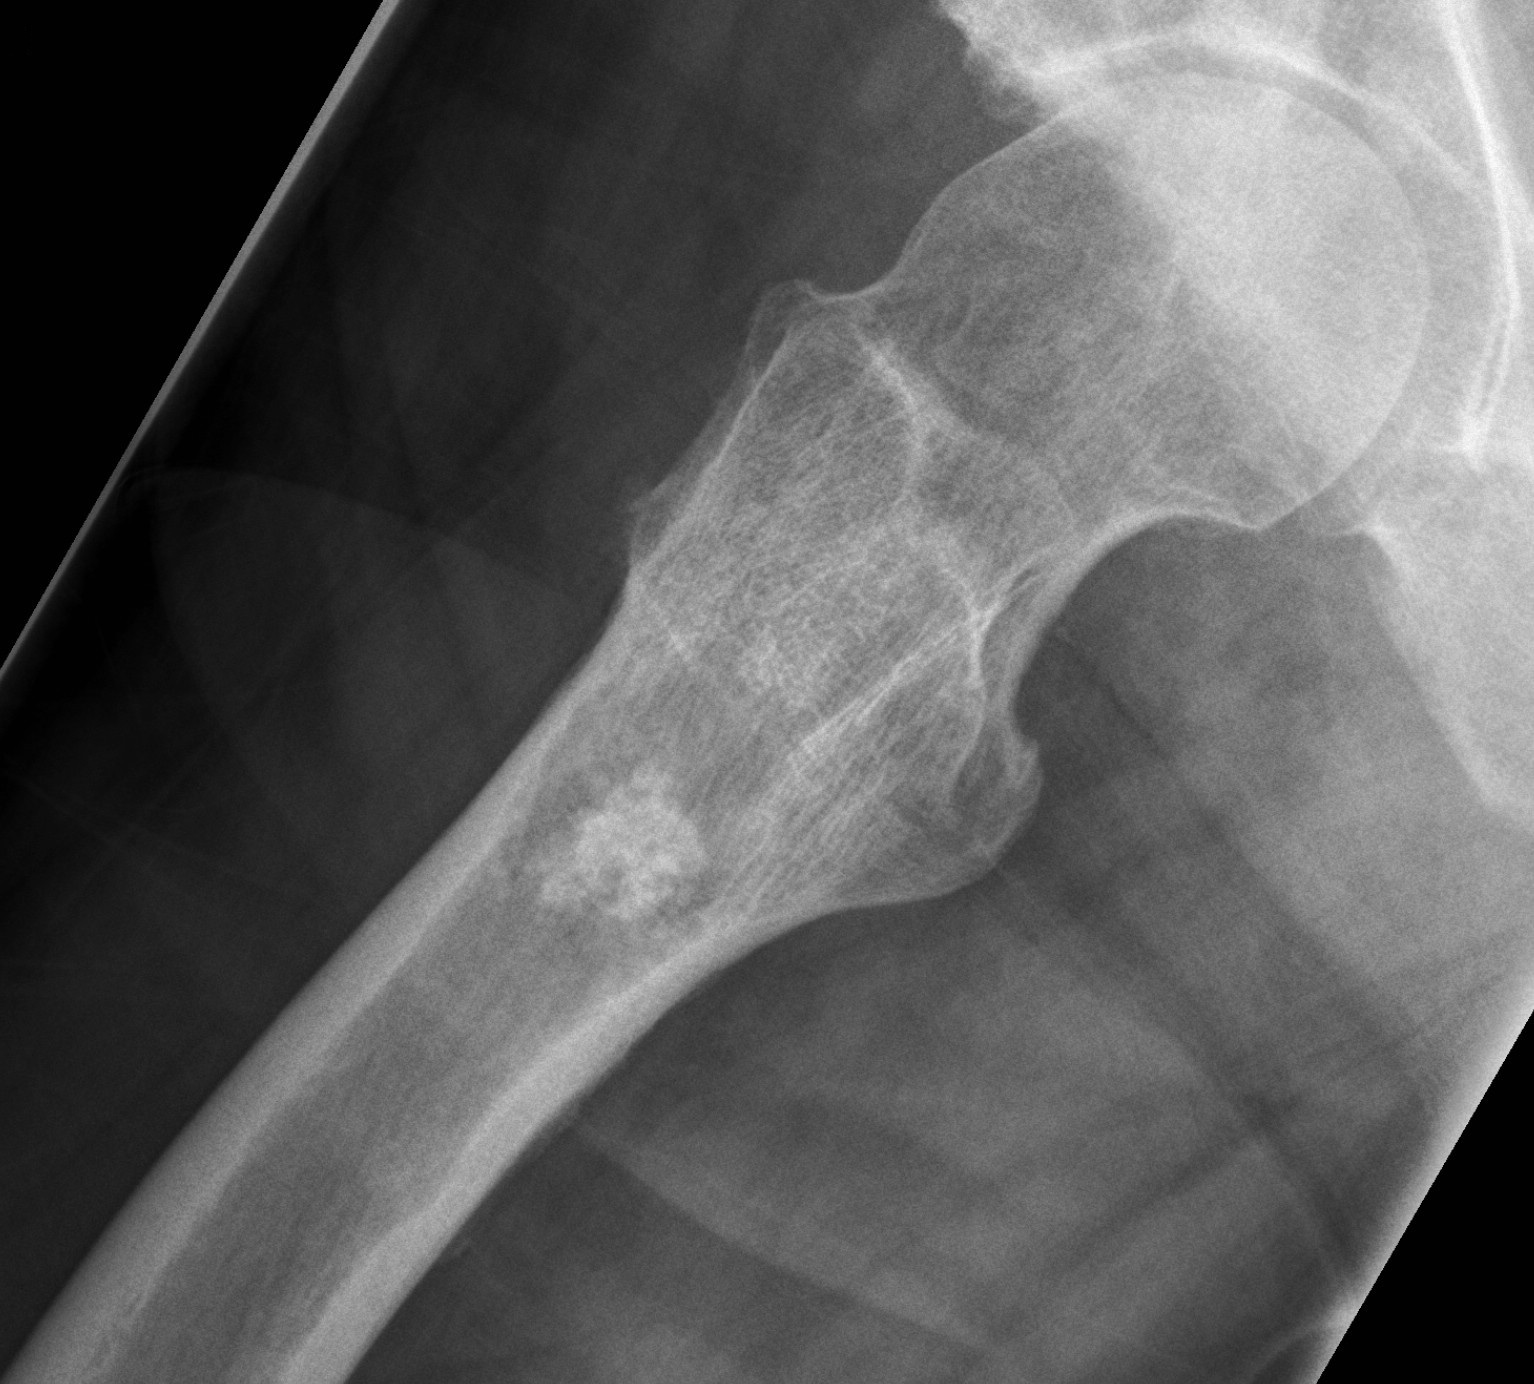

Саркома На Ноге ФотоВыберите Ваш пол👨 👉🏻👉🏻👉🏻МУЖЧИНА👈🏻👈🏻👈🏻👩🦱 👉🏻👉🏻👉🏻ЖЕНЩИНА👈🏻👈🏻👈🏻Саркома На Ноге Фото (90 фото)